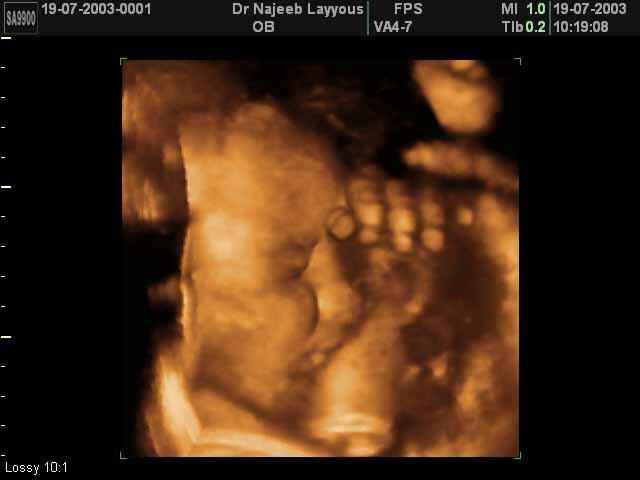

- صور جانبية لرأس الجنين

صور جانبية لرأس الجنين بجهاز الالتراساوند ثلاثي الأبعاد | الدكتور نجيب ليوس